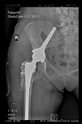

The direction of the cup stem was determined by the guide wire. The aiming device was needed to introduce this wire. After removing the aiming device, the next step was the drilling. Since a cannulated drill bit was used, the previously installed wire could guide the process. A self-positioning reaming tool was then used in the drilled channel. In the prepared cavity, the cup was fitted perfectly. Of the two stemmed cups available to us, the McMinn cup (Waldemar Link, Hamburg, Germany) had the simpler geometry and was therefore chosen. The stemmed cup was inserted according to the manufacturer’s recommendation. In the presence of a significant bone defect, a synthetic bone graft may be impacted for substitution.

The radiological examination allowed us to verify the close bone-to-implant contact and the unchanged position of the implant during follow-up.

In all the cases operated with the above-described targeting procedure, the stems of the cups remained between the cortical bone surfaces without perforation of the linea terminalis, as shown by postoperative radiographs. There were no complicated surgical situations. In 16 cases, the wound healings were uneventful, and the hips were able to bear weight again after postoperative rehabilitation.